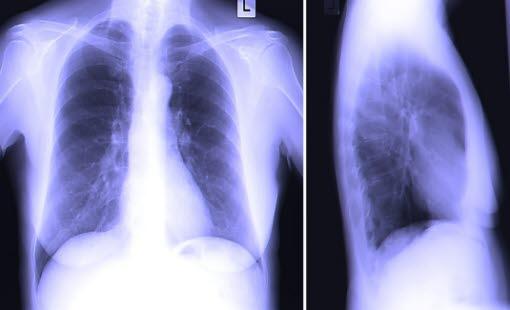

Røntgen eller CT av brystkassen er de undersøkelsene som stadfester diagnosen. Funnene er vanligvis så typiske at diagnosen er klar. CT-undersøkelsen er avgjørende for å klarlegge alvorlighetsgraden av sykdommen. Endelig bekreftelse krever analyse av en vevsprøve fra svulsten.